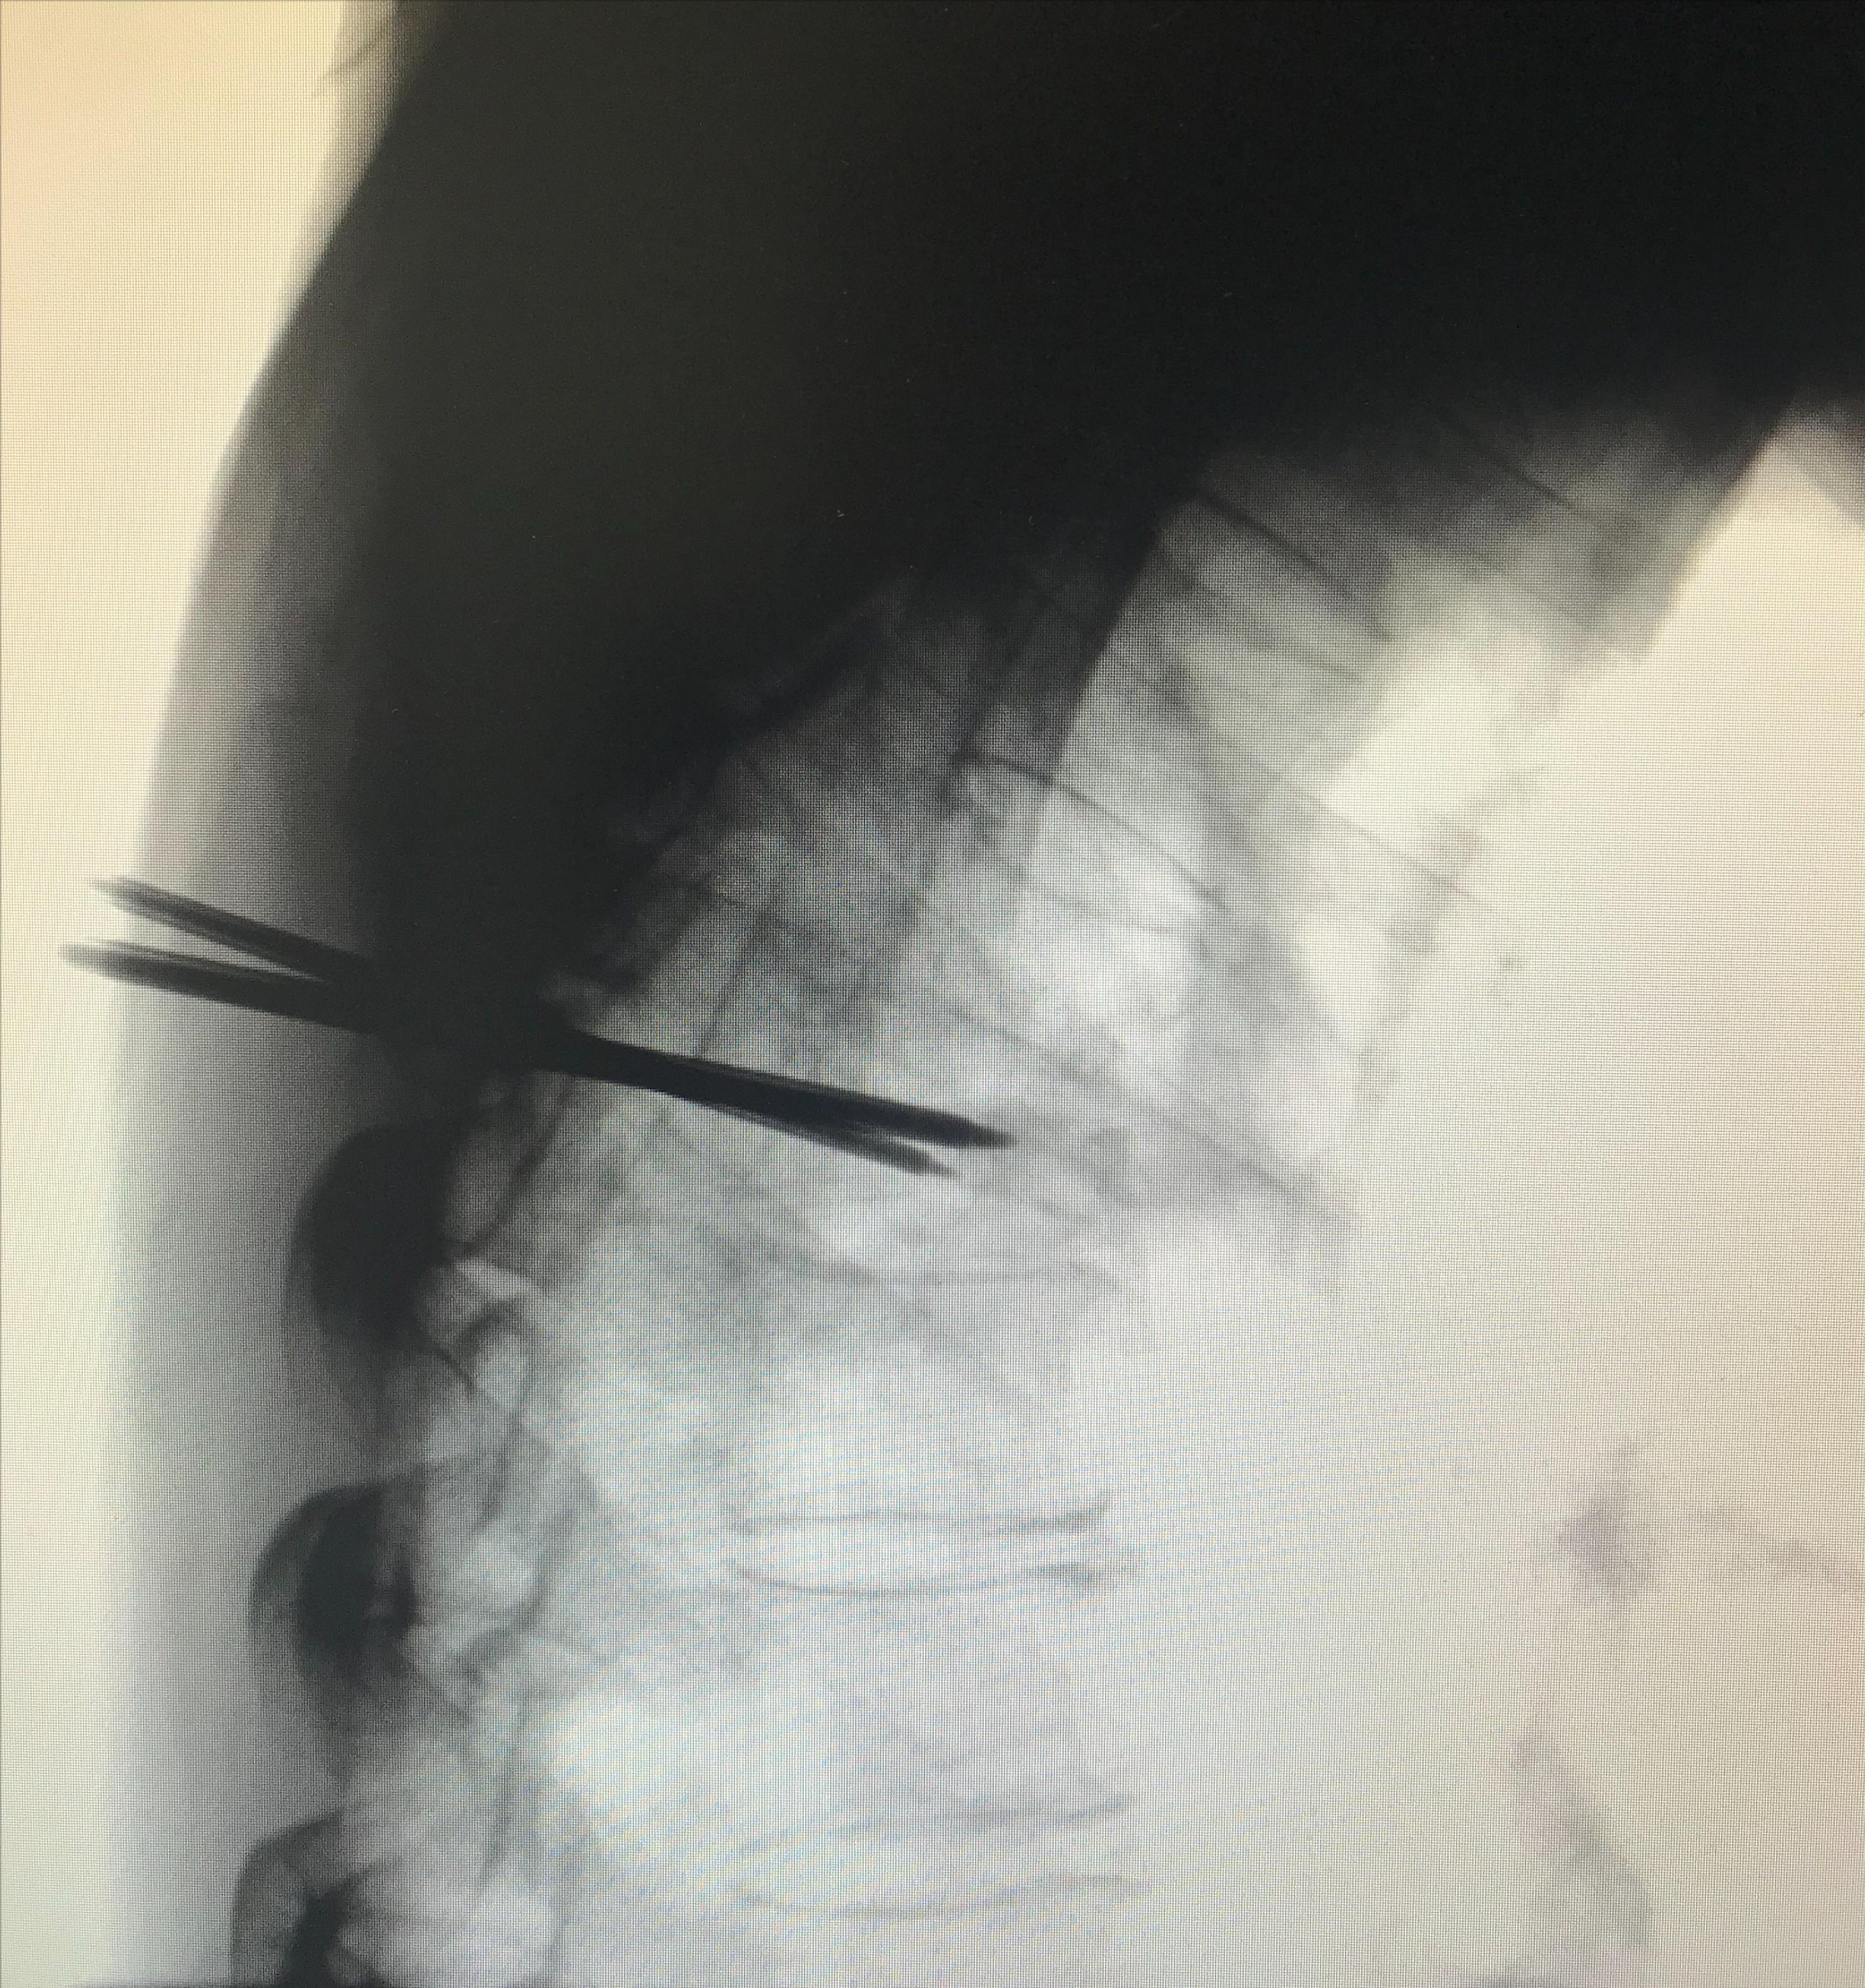

DSA引导下双侧椎弓根入路置针成功(侧位)